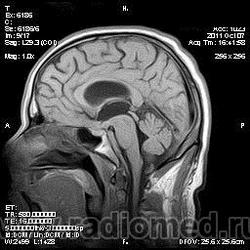

на МРТ - Определяется скопление крови в препонтинной цистерне, в проекции супраселлярной цистерны, в кортикальных бороздах полушарий головного мозга,  в проекции краниоспинального перехода. Выявляется горизонтальный уровень крови в задних рогах боковых желудочков. Боковые, третий желудочки резко расширены. Определяется перивентрикулярное повышение интенсивности сигнала от белого вещества головного мозга. Срединные структуры не смещены. Кортикальные борозды умеренно сглажены. Сильвиев водопровод прослеживается на всем протяжении. Отмечается смещение дна третьего желудочка каудально, с резким уменьшением размеров супраселлярной цистерны; базальные цистерны уменьшены в размере.

В проекции базальной артерии определяется аневризма размером до 4х6 мм.